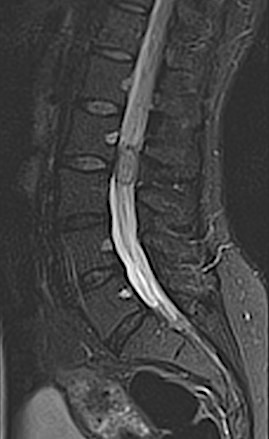

Paciente de 46 años con historial oncológico de cáncer de mama en remisión completa que presenta LOE en cauda equina tras realizar RM por parestesias en MMII.

En informe de RM fue diagnosticado como lesión sugestiva de schwannoma, ependimoma o (menos probable) meningioma. La paciente fue intervenida con monitorización neurofisiológica intraoperatoria y la lesión carecía de cápsula e «infiltraba» las raíces, por lo que se realizó una exéresis incompleta con caída parcial de potenciales que recuperó en pocas semanas. La AP demostró la malignidad del cuadro.

En los cortes axiales se aprecia la lesión ocupando casi todo el volumen tecal, con desplazamiento de raíces a anterior y lateral. Obsérvese el aspecto festoneado de la masa, poco habitual en tumores capsulados